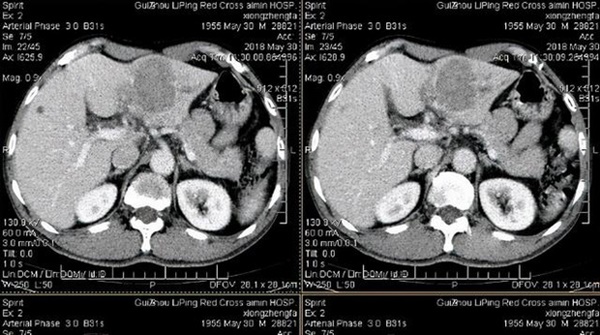

Qua kiểm tra, chỉ số alpha-fetoprotein (AFP) của ông Wu và con trai cao tới 500ng/ml, cuối cùng họ được chẩn đoán là mắc bệnh ung thư gan, sau khi hỏi ý kiến bác sĩ thì hóa ra gia đình ông Wu gặp vấn đề rất nghiêm trọng trong thói quen ăn uống hàng ngày.